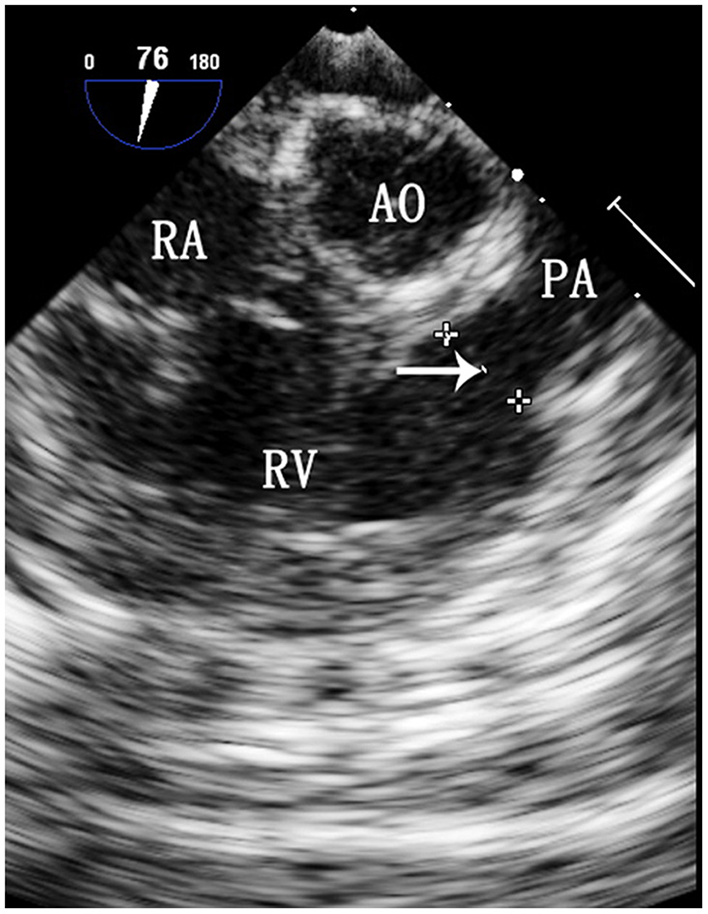

Selection of the ASD occluder and PS balloon. ASD occluder: The maximum diameter of the ASD was measured on a four chamber heart section and a two atrial chamber section via intraoperative esophageal ultrasound. Generally, we added 2–4 mm to the maximum diameter measured on the two atrial chamber section (Figure 3) to determine the ASD occluder size. Balloon: Esophageal ultrasound was used to simultaneously show the right ventricular outflow tract and pulmonary artery to measure the maximum diameter of the pulmonary valve annulus (Figure 4), and a balloon size 1.2–1.4 times the measured value was used.

Figure 4

TEE image of the maximum diameter of the pulmonary valve annulus. RA, right atrium; Ao, aorta; RV, right ventricle; PA, pulmonary artery. The arrow indicates the maximum diameter of the pulmonary valve annulus.